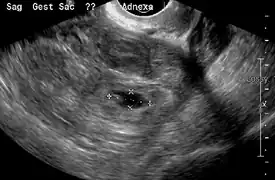

An ultrasound showing a gestational sac with fetal heart in the fallopian tube has a very high specificity of ectopic pregnancy. Transvaginal ultrasonography has a sensitivity of at least 90% for ectopic pregnancy.[4] The diagnostic ultrasonographic finding in ectopic pregnancy is an adnexal mass that moves separately from the ovary. In around 60% of cases, it is an inhomogeneous or a noncystic adnexal mass sometimes known as the "blob sign". It is generally spherical, but a more tubular appearance may be seen in case of hematosalpinx. This sign has been estimated to have a sensitivity of 84% and specificity of 99% in diagnosing ectopic pregnancy.[4] In the study estimating these values, the blob sign had a positive predictive value of 96% and a negative predictive value of 95%.[4] The visualization of an empty extrauterine gestational sac is sometimes known as the "bagel sign", and is present in around 20% of cases.[4] In another 20% of cases, there is visualization of a gestational sac containing a yolk sac or an embryo.[4] Ectopic pregnancies where there is visualization of cardiac activity are sometimes termed "viable ectopic".[4]

Transvaginal ultrasonography of an ectopic pregnancy, showing the field of view in the following image.

Ultrasound image showing an ectopic pregnancy where a gestational sac and fetus has been formed.